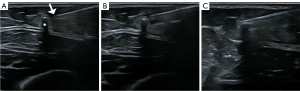

In cases where the implant is situated in a non-palpable deep position, ultrasound is the primary method for localization, specifically evaluating whether the implant is positioned above or below the fascia and its proximity to the surrounding neurovascular structures (13). Through ultrasound, the implant is in most cases easy to find, especially in the transverse plane of the probe relative to the rod. Implanon NXT®/Nexplanon® implants are visualized as an echogenic dot (transverse plane) or linear structure (longitudinal plane) with a diameter of 2 mm and robust posterior acoustic shadow (14). Jadelle® double-rod devices are visualized as tubular hypoechoic structures, also with posterior acoustic shadowing (Figure 1A-1C).